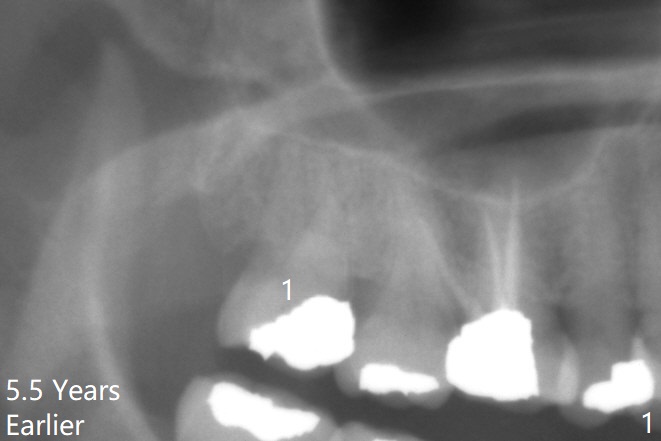

智齿与上颌窦囊肿       Last     Next